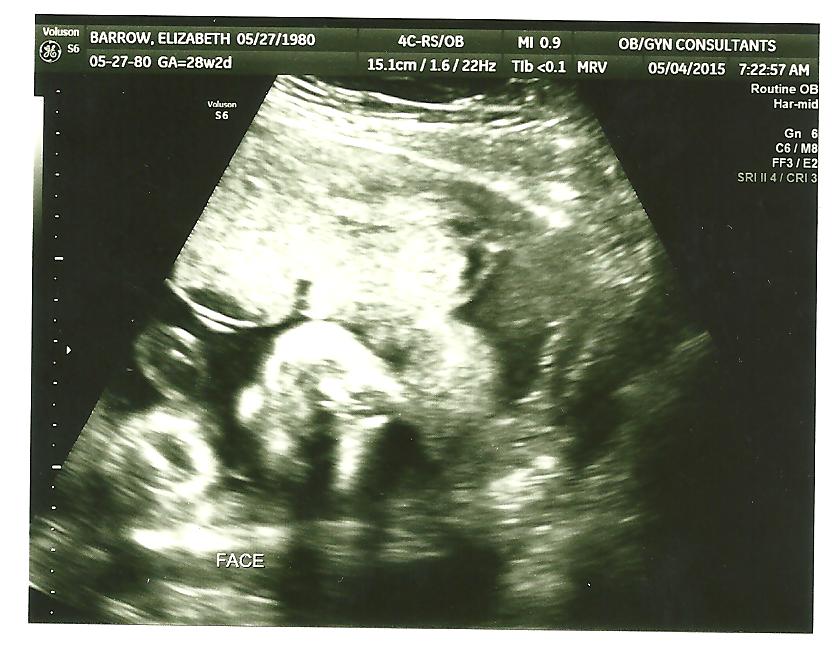

Best moment this week: The ultrasound, of course. I seriously was stressing about it because we had a red flag on our last ultrasound, but everything was measuring great. He is 2 pounds 11 ounces right now and dead on for all of the other stats! Phew. I thought that the stress of the Chicago trip would have caused something!

(Another face shot. Sideways. Ultrasounds are creepy.)

Gender prediction: Boy. Mike was able to see the parts again during the ultrasound and congratulated him for staying a boy.

The large kickers!